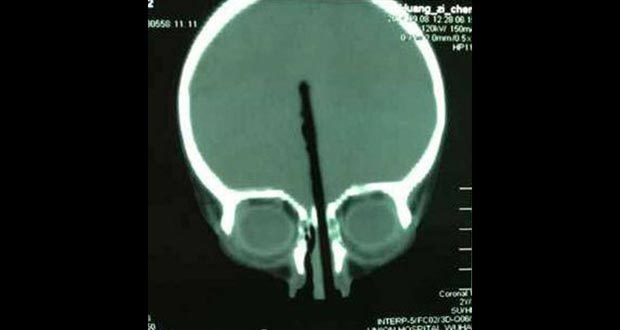

نجح أطباء صينيون في إخراج عصا من رأس طفل كان قد غرزها في أنفه لتخترق نحو 8 سنتيمترات من دماغه.

ونقلت صحيفة الشعب الصينية عن والد الطفل البالغ من العمر عامين قوله إنه لا يعرف كيف أو لماذا غرز طفله عصا الطعام في أنفه مخترقة ما يقرب من 8 سنتيمترات داخل دماغه.

وقد نقل الطفل هوانغ إثر ذلك إلى مستشفى في مقاطعة هوبي الصينية حيث أجرى الأطباء جراحة عاجلة استغرقت نحو أربع ساعات كاملة ونجحوا في إخراج العصا من رأسه دون ان تعطل أيا من الأعصاب أو الشرايين داخل دماغه.